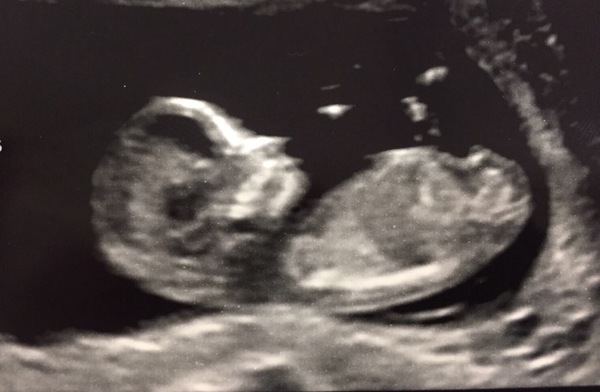

Scan was all okay, 2 healthy non-ID twins.

They put me forward a week to 13+3 so my new due date is 19th of march. That's impossible from my ovulation dates so they must be measuring big!

Lovely scan @mrskitty15, glad it went well Smile